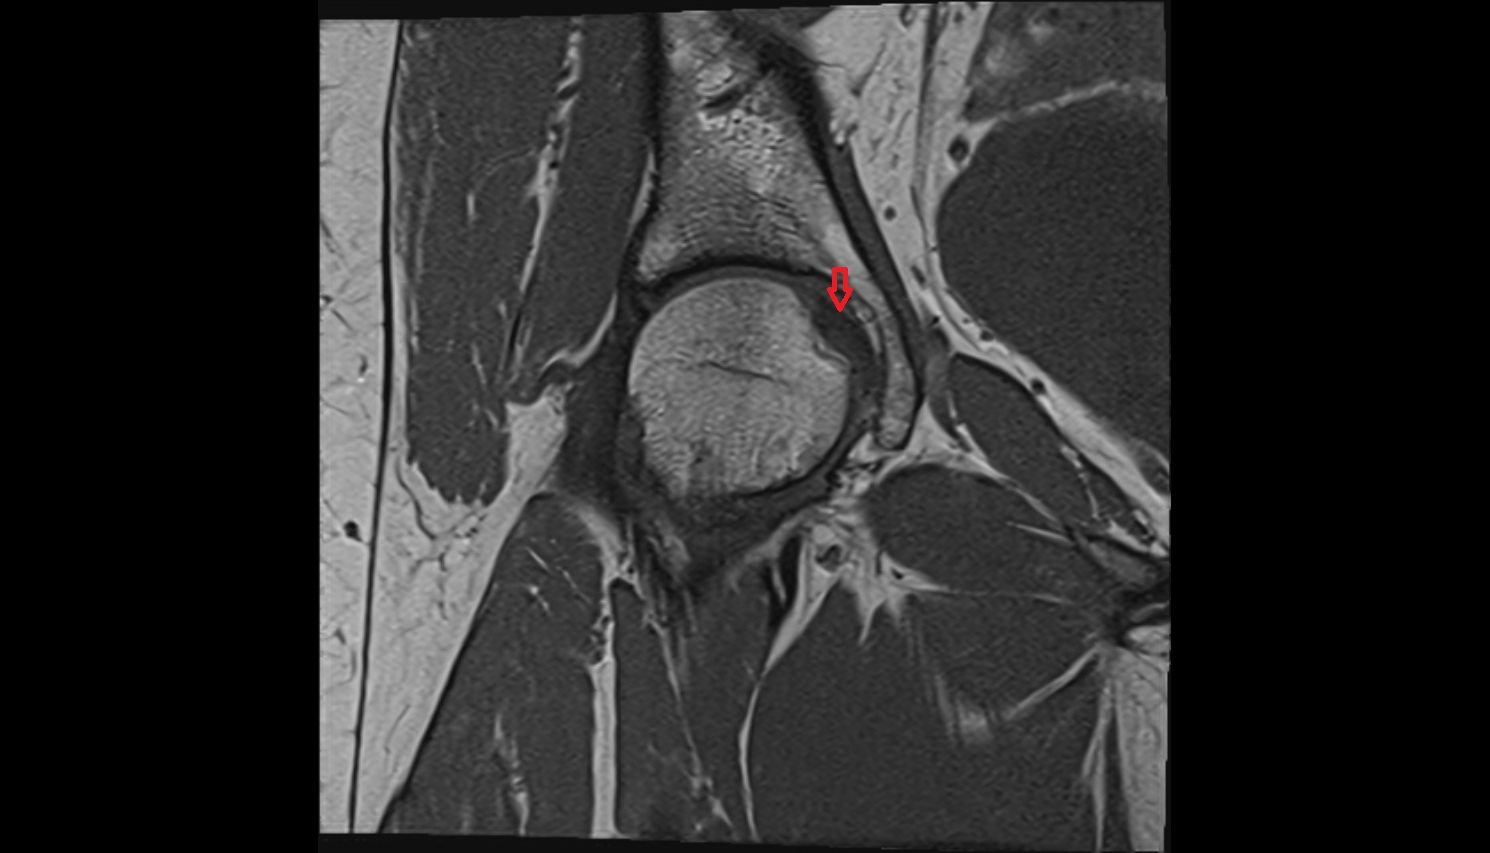

- Acetabular labrum

- Medial collateral ligament

- Medial meniscus

- Lateral meniscus

- Knee Joint